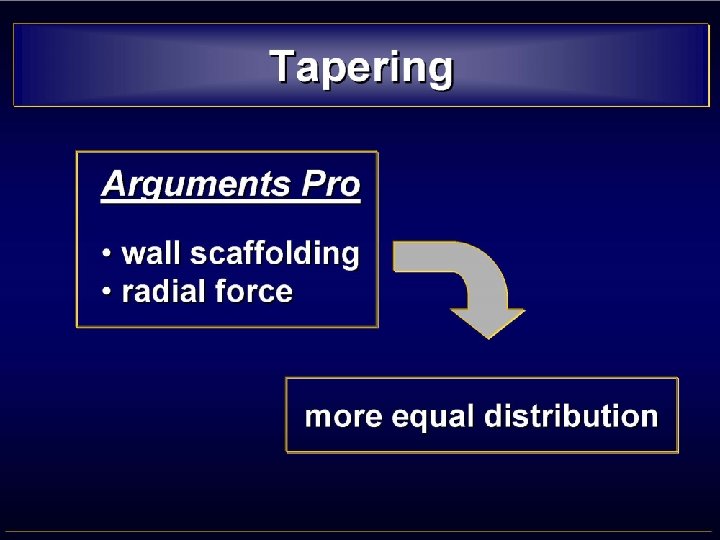

• MISMATCH CCA-ICA